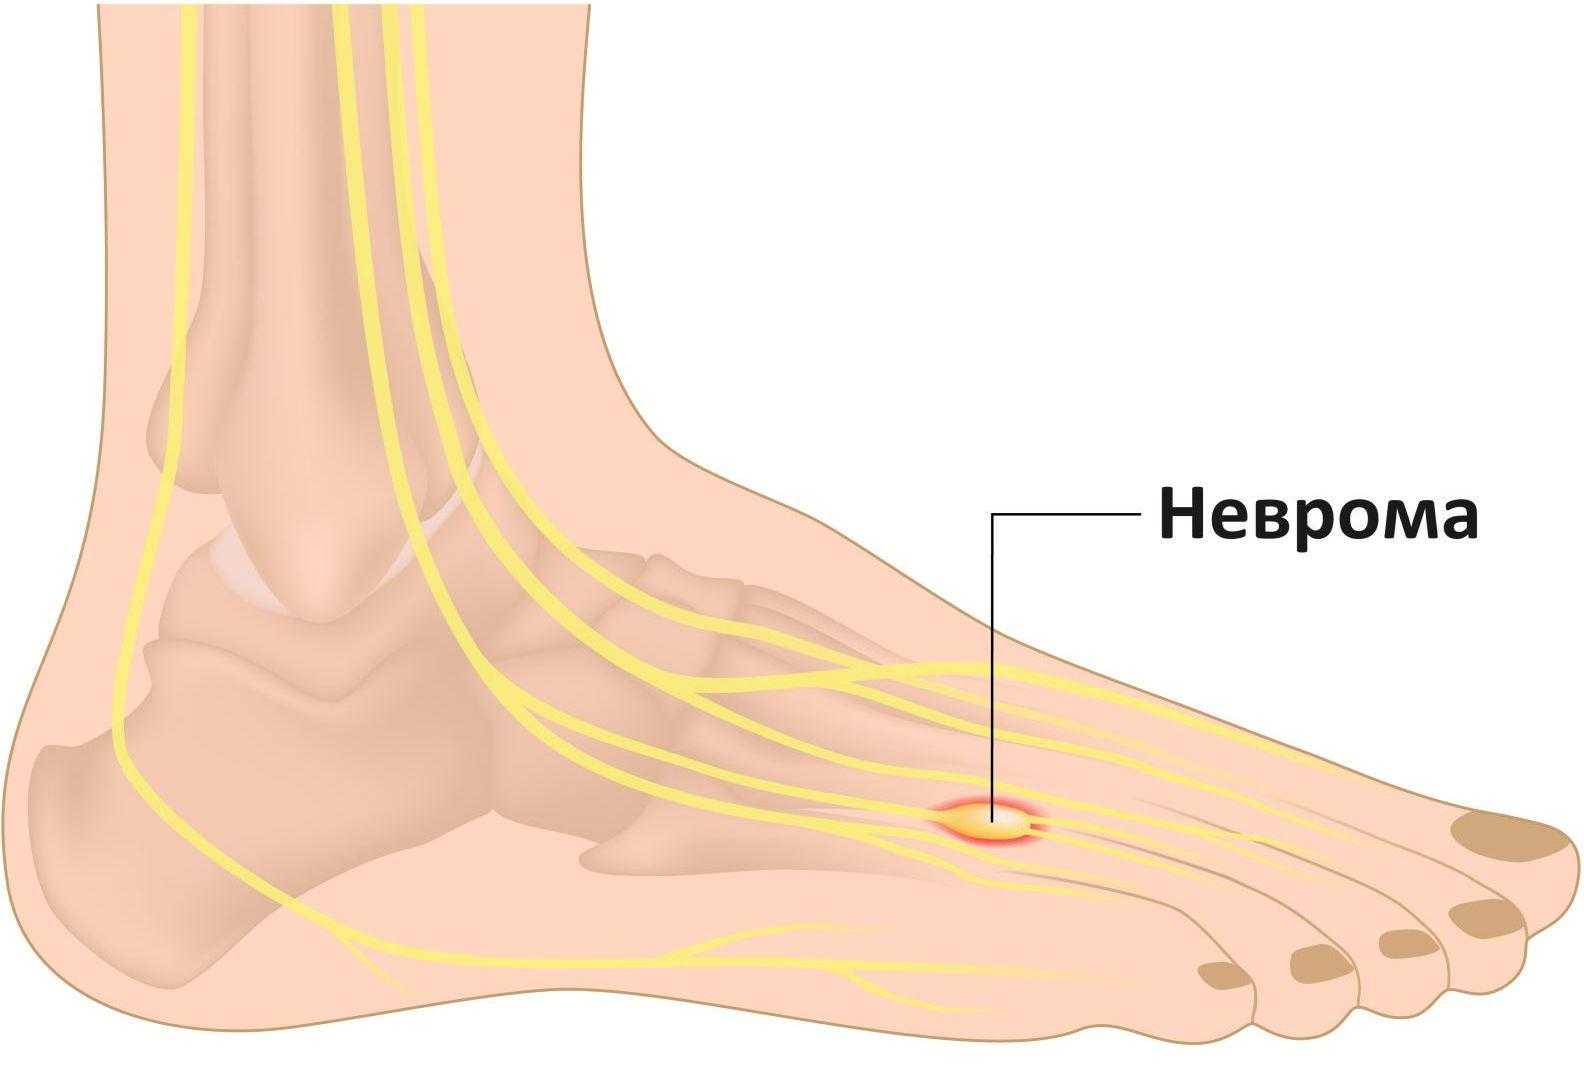

Разрастание нервной ткани, расположенной на подошве ноги, между 3-и и 4-м пальцами, называется невромой Мортона. Что это такое? Это фиброзное доброкачественное новообразование обычно поражает одну ногу, редко – обе сразу.

Заболевание проявляется в виде утолщения нерва на подошве, это сопровождается сильными болями, резко ограничивает человека в передвижениях. Когда у врачей появляется подозрение на развитие метатарзалгии Мортона, это говорит об опухолевом новообразовании нервной ткани, вызывающем сильные боли в плюсневых сочленениях.

Эти заболевания ведут к ущемлению нервных окончаний, из-за чего образуются отеки, происходит патологический рост оболочки нервных волокон. Им становится сложно умещаться между связками ступни.